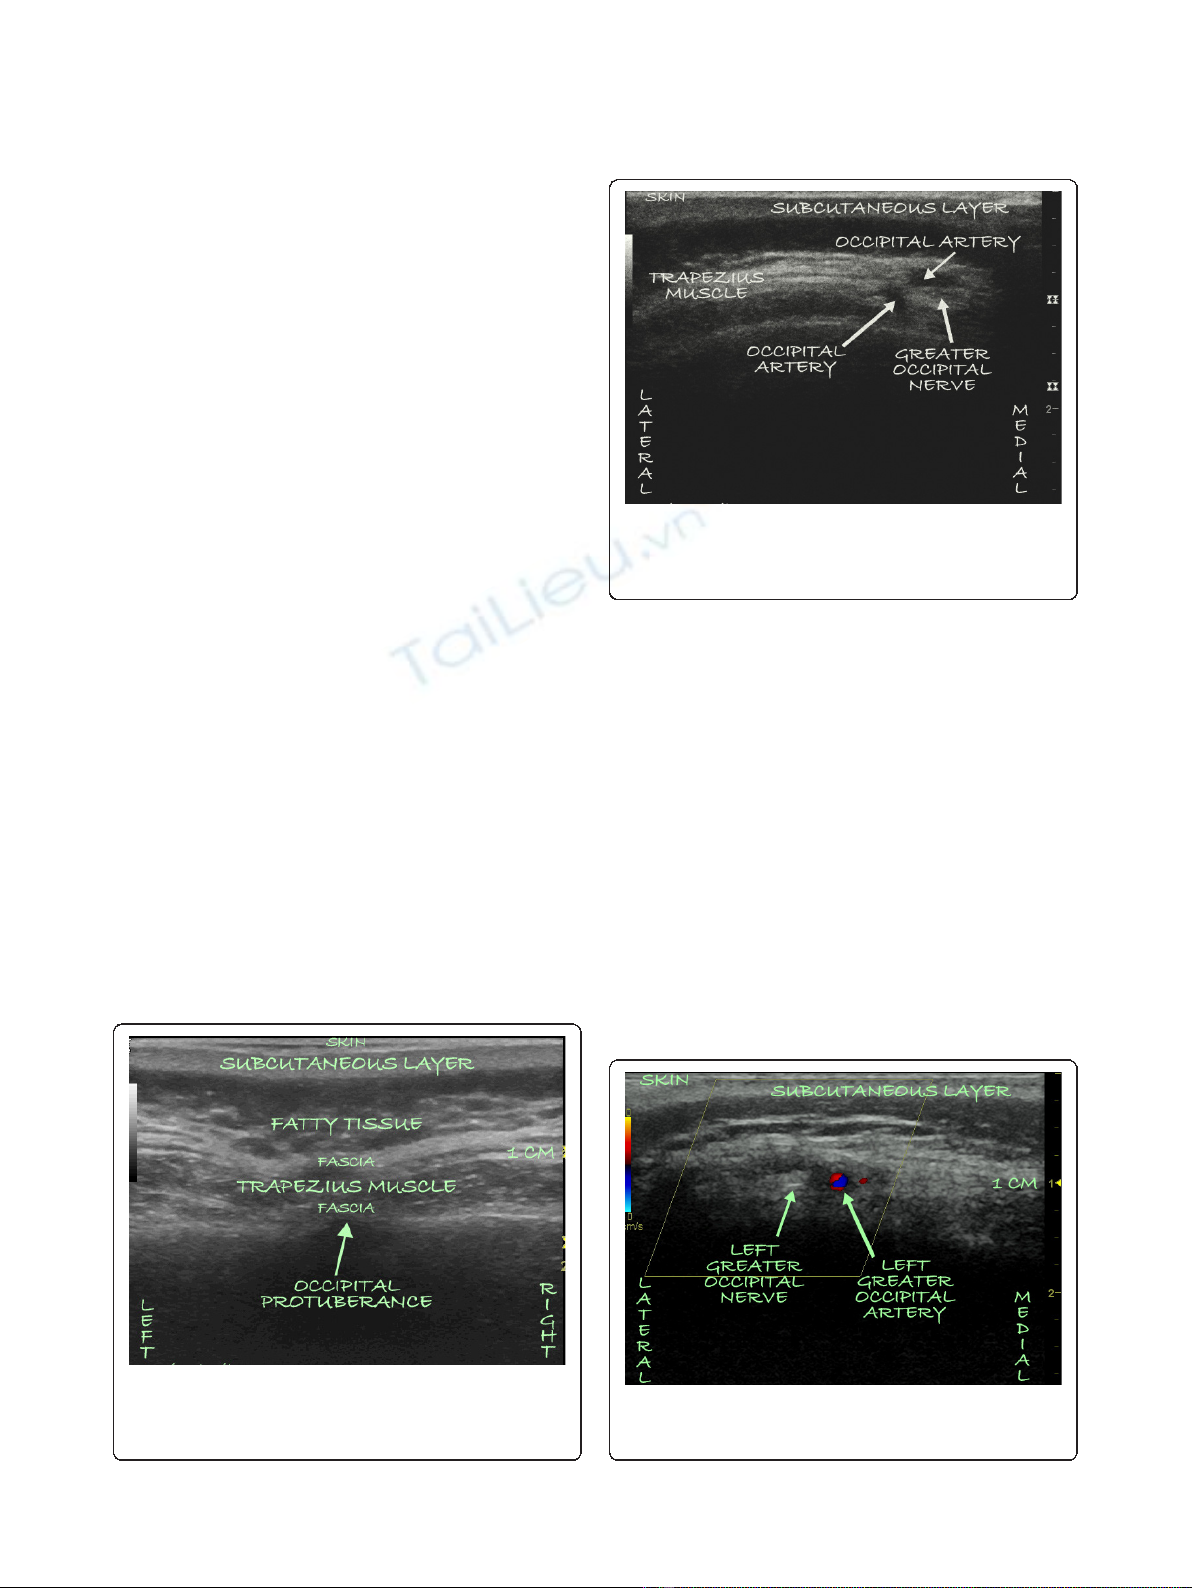

frequency was placed to obtain images of the bilateral

occipital fossae and the bilateral greater occipital nerves

and arteries. The ultrasound probe was first placed at

the midline just below the external occipital protuber-

ance (Figure 1). The probe was slowly advanced laterally

at the same level until the greater occipital artery and

nerve were visualized as two distinct structures: the

artery as a hypoechogenic oval structure and the nerve

as a hyperechogenic structure (Figures 2 and 3). The

nerve could be traced from its exiting trunk into two

distinct divisions within the substance of the trapezious

muscle. The artery was identified by using Doppler

ultrasound(Figure2).Thelocationsofthenerveand

thearteryweremarkedbilaterallyontheskinwitha

sterile marker. The depths of both the artery and the

nerve were found to be consistent at 1.0 cm to 1.2 cm

Figure 2 An ultrasound image of the left occipital nerve as

well as two divisions of the greater occipital artery as they

pierce the substance of the trapezious muscle 1.0 cm to 1.2

cm from the skin.

Figure 3 A Doppler ultrasound image of the left occipital

nerve and artery as they pierce the substance of the trapezius

muscle side-by-side 1 cm from the skin.

Of interest is the fact that during ultrasound guidance

for OPNS, the greater occipital nerve was visualized

both medially (Figure 2) and laterally (Figure 3) to the

greater occipital artery. The variable course of the

greater occipital nerve as it relates to the greater occipi-

tal artery, as well as the ability of ultrasonography to

accurately identify both structures, makes a strong argu-

ment for the utilization of ultrasound guidance.